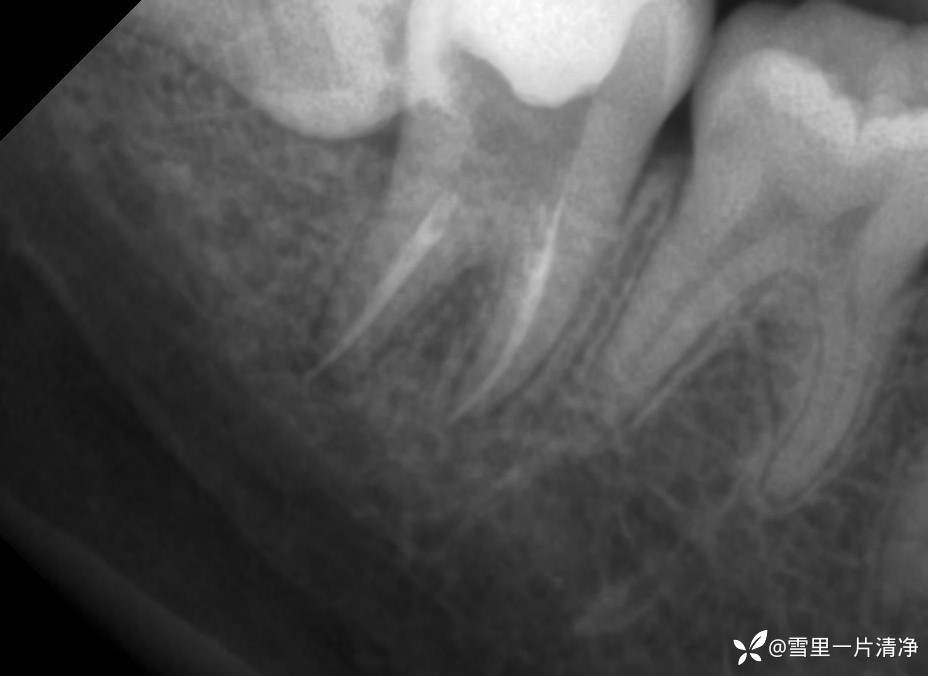

2号片子,7号牙无松动,根干完整,先拔除8再进行7号牙的治疗

这是雪梨,血的教训!后牙拔除8 的时候辛辛苦苦的龈壁提升,被自己搞掉了,还带了部分牙出来

2号片子